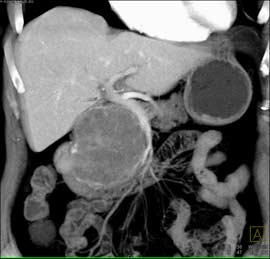

The best dx in this case in a 60 year old female is?

pseudocyst

serous cystadenoma

mucinous cystadenoma

SPEN tumor